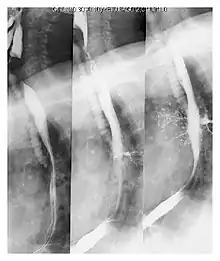

| Upper gastrointestinal series at the level of the esophagus, showing pulmonary aspiration of the radiocontrast agent | |